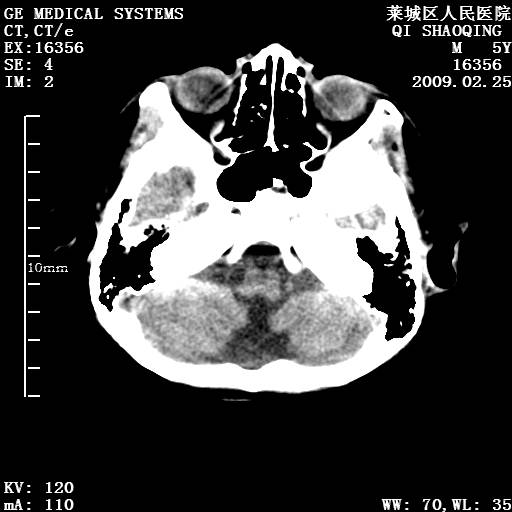

以下是引用wangzhengyuan在2009-2-28 10:22:00的发言:[br]甲状旁腺功能减退引起的脑改变.

以下是引用zsl6918在2009-2-28 10:17:00的发言:[br]首先考虑甲状旁腺功能低下所致,可结合实验室检查明确.另外需除外先天性宫内感染所致.

以下是引用余辉在2009-3-1 9:35:00的发言:[br]患者明显的肢体及智力改变,不支持fahr病,多考虑甲旁低,有可能伴有甲低(呆小症).进一步检查。